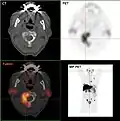

- TEP/scanner à la choline 18F

Métastases ostéolytiques dans la deuxième vertèbre du cou (Axis) d'un cancer de la prostate.

Métastase ostéocondensante d'un cancer de la prostate dans la hanche

Scanner d'une métastase d'un cancer de la prostate à gauche dans le pubis (à dr. sur l'image)

TEP de la même métastase au pubis

Image composite scanner/TEP de la même métastase